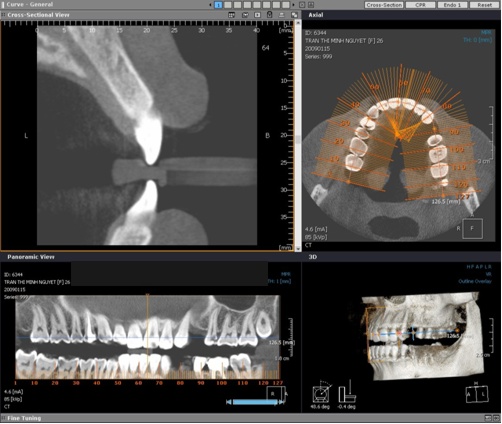

Chụp phim Panorama kiểm tra

![]() |

| Phim Panorama |

| Phim X quang cắt lớp 3 chiều |

Dựa trên phim Panorama ta có thể thấy R24 bị tiêu xương ổ răng do mất răng lâu ngày

Kế hoạch điều trị: cấy 1 implant nâng đỡ R24, ghép xương

Kiểm tra mật độ xuơng ổ R24 trên phim CT 3 chiều và phần mềm cấy ghép Implant

| Xác định chiều rộng và chiều dài xuơng ổ răng |

Chiều dài: 16.6mm

Chiều rộng: 2.0mm